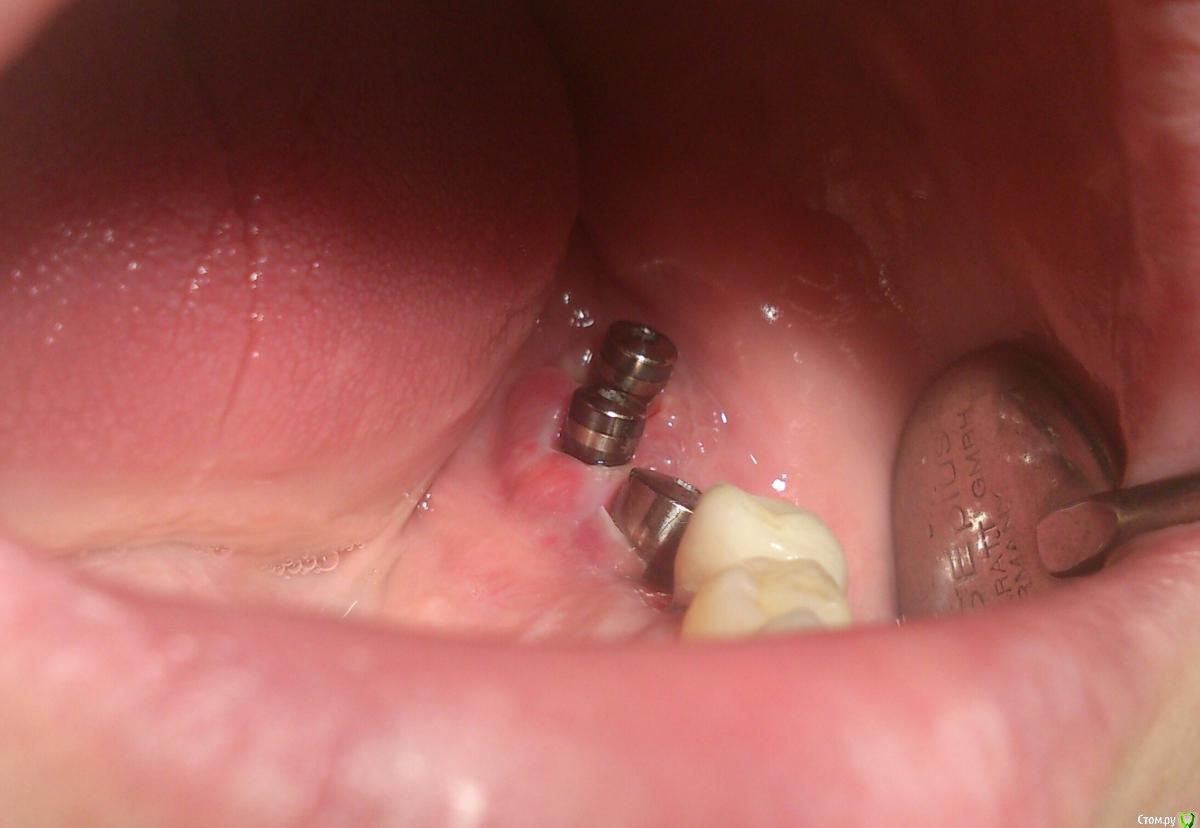

andrey_1965 Опубликовано 21 декабря, 2015 Поделиться Опубликовано 21 декабря, 2015 Ну как результат ?1.-диэпителизация подворот лоскута очень удобно,но опасно для резбы через неделю.язычно-механическая травма через 10 дней через 3недели. На временных доформирую рельеф.2. вроде ничего нештатного через 2недели A-PRF через 5недель убрал все,закрыл мембраной A-PRF две поперек,одна в доль через неделю через 13дней через 21день. Следующий осмотр будет на сроке 5 недель(думаю все сравняется) 3. через неделю 2недели 3недели,на дистальных отмываю помойку4 недели Ссылка на комментарий